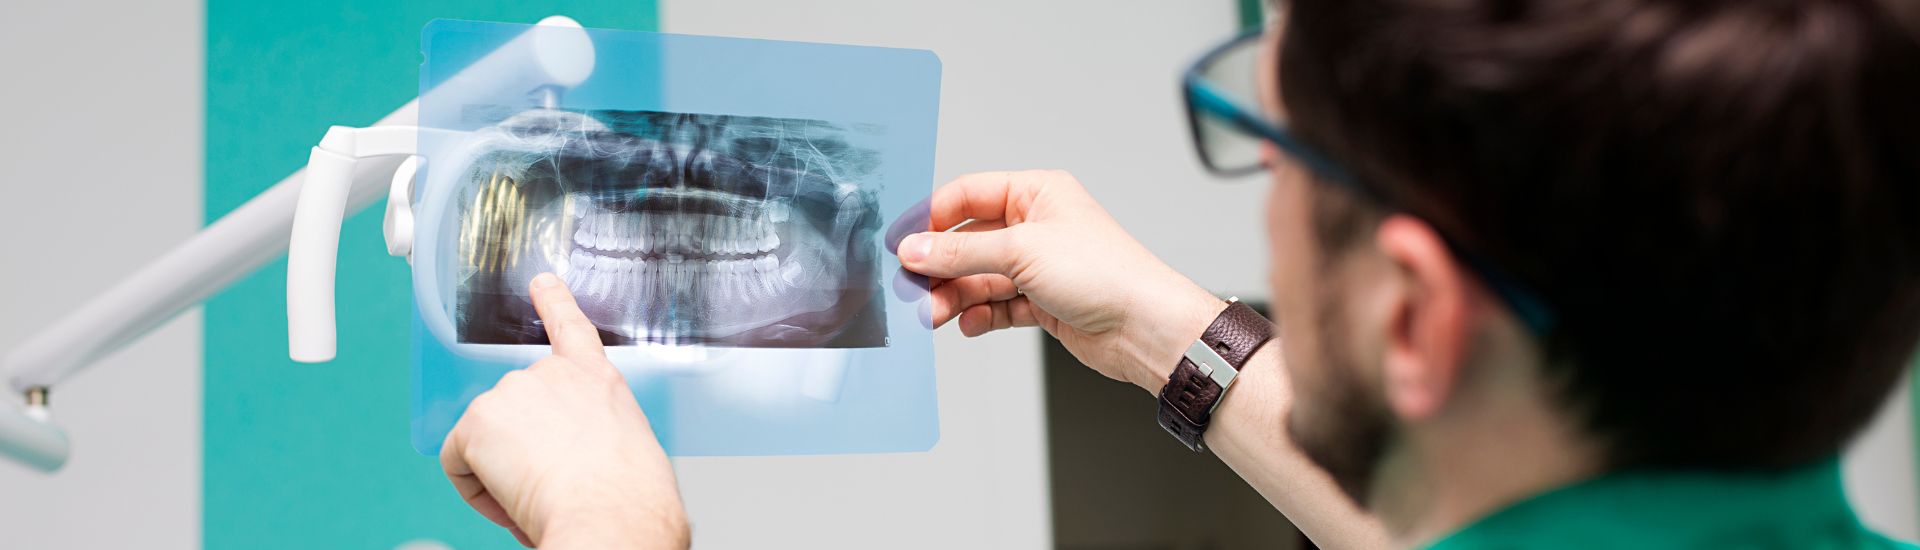

Durante l’esame di Teleradiografia, il paziente viene invitato a posizionarsi di fronte all’apparecchiatura radiografica, che acquisisce le immagini del cranio attraverso una rotazione intorno alla testa. Questa tecnica consente di ottenere una visione completa della struttura scheletrica e dentale, essenziale per rilevare anche le minime irregolarità. L’intera procedura dura solo pochi minuti e non richiede alcun tipo di anestesia o preparazione specifica, rendendola particolarmente adatta a tutti i tipi di pazienti.

In genere, l’esame di Teleradiografia non richiede alcuna preparazione particolare. È comunque importante informare il medico di eventuali condizioni mediche preesistenti, come la gravidanza o allergie specifiche. Al momento dell’esame, potrebbe essere necessario rimuovere oggetti metallici, come occhiali o protesi dentali rimovibili, per evitare distorsioni nelle immagini.